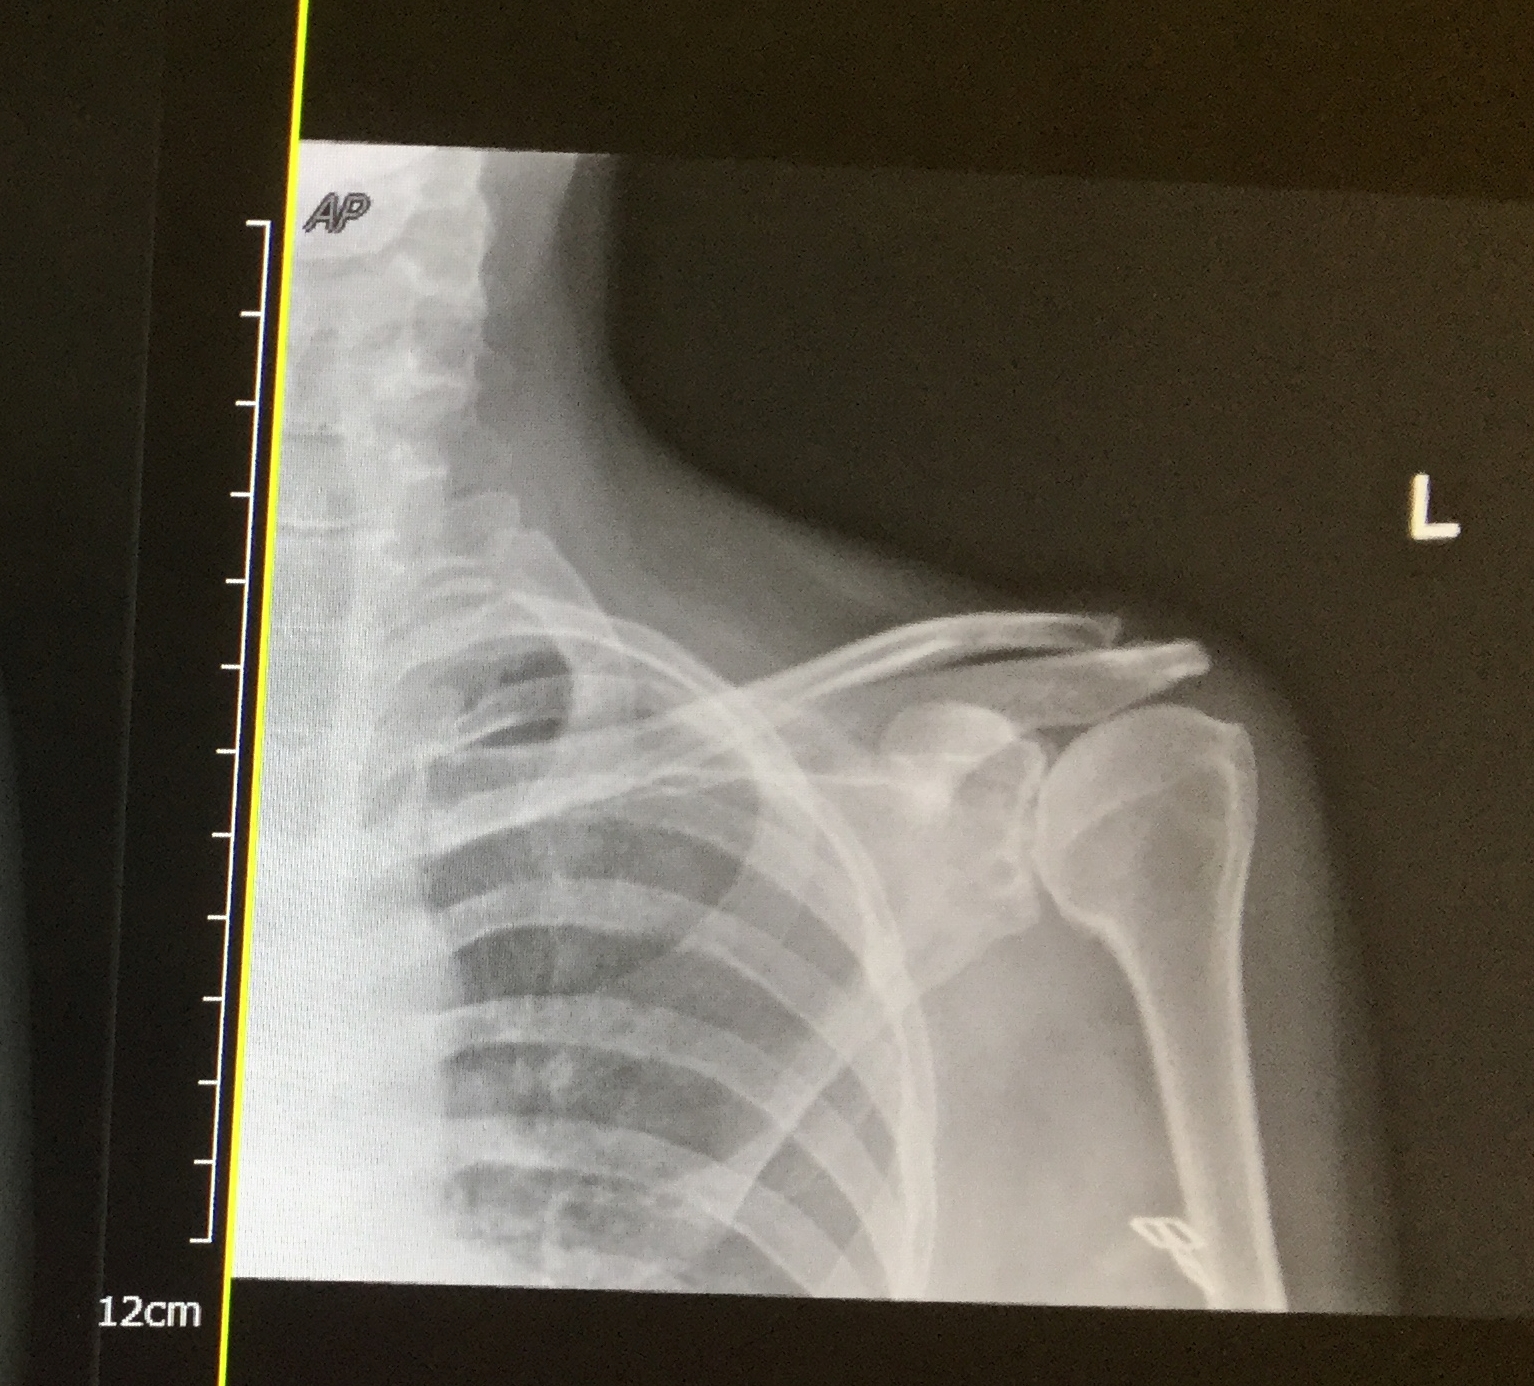

Gallery 27 Wednesday Jan 2016 Original size at 1534 × 1386 ≈ Leave a comment My X-ray Before Op Please share this: Email a link to a friend (Opens in new window) Email Tweet Share on WhatsApp (Opens in new window) WhatsApp Like Loading...